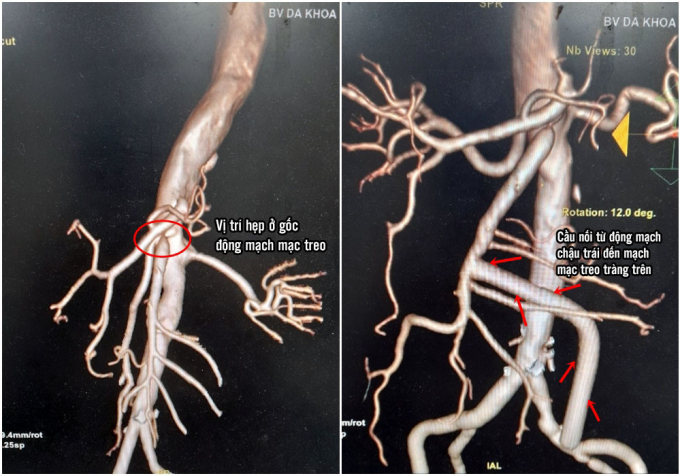

Nghi ngờ bệnh lý liên quan đến mạch máu ruột, các bác sĩ đã chỉ định chụp cắt lớp mạch máu ổ bụng, kết quả phát hiện thành động mạch chủ bụng xơ vữa vôi hoá, trong có nhiều huyết khối bám thành, động mạch thân tạng và động mạch mạc treo tràng trên bị hẹp ở gốc do xơ vữa.

Hình ảnh trước và sau khi phẫu thuật ( ảnh Bệnh viện )

Các bác sĩ tiến hành bộc lộ động mạch chậu chung bên trái còn mềm mại và gốc động mạch mach treo tràng trên sau chỗ hẹp, tiến hành nối động mạch chậu và động mạch mạc treo tràng trên bằng đoạn mạch nhân tạo luồn qua đường hầm sau phúc mạc.